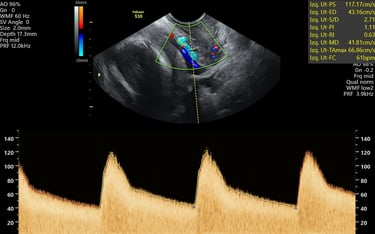

ecografía de crecimiento Doppler

24 - 40 semanas